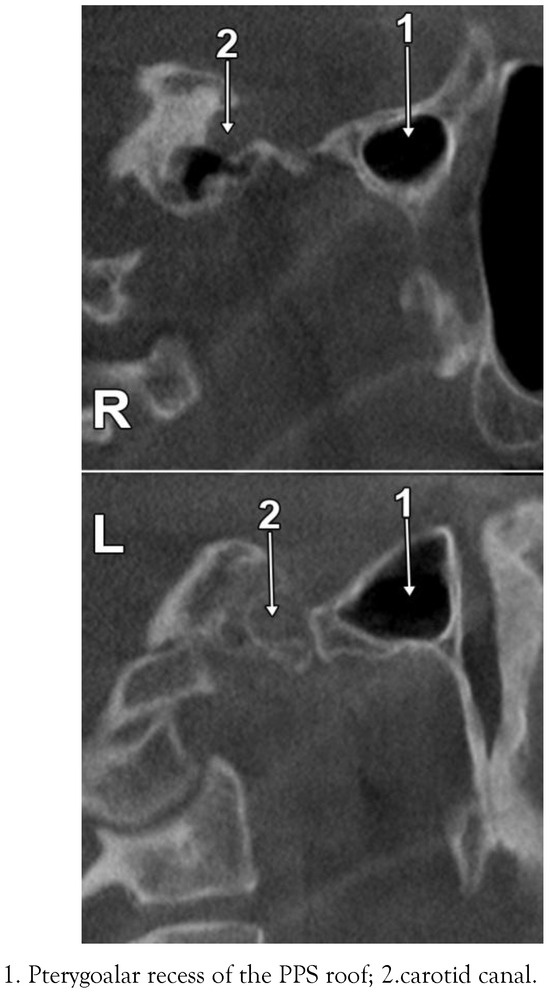

The Pneumatization Patterns of the Roof of the Parapharyngeal Space in CBCT

Introduction: The rhinopharynx and the parapharyngeal space (PPS) are complex anatomical territories located beneath the skull base. Thorough knowledge of the complex anatomy of the PPS is essential in treatment of pathologies such as parapharyngeal abscesses. The roof of the PPS is overlooked in anatomy. It was hypothesized that the pneumatization pattern of the PPS roof is individually variable, as determined by the variable pneumatization patterns of the sphenoid and temporal bones. The study was aimed at assessing the anatomy of the PPS roof in CBCT. Methods: The present study was performed retrospectively on a group of 35 subjects (37.1% males) evaluated by CBCT for various dental procedures. Results: The mean age of the group was 37.9 (SD: 14.2, range: 18 to 61). The major bony landmarks of the PPS roof were: the petrous apex with the carotid canal, the jugular foramen, the foramen lacerum, the sphenopetrosal fissure or suture, and the root of the pterygoid process. Variable patterns of pneumatization were determined by the petrous apex air cells and the pterygoalar recess of the sphenoidal sinus. As related to the individually pattern of pneumatization, the following types of the PPS roof were defined: (i) type 1 – not pneumatized PPS roof; (ii) type 2 – sphenoidal but not petrosal pneumatization of the PPS roof; (iii) type 3 – petrosal but not sphenoidal pneumatization of the PPS roof; (iv) type 4 – sphenoidal and petrosal pneumatizations of the PPS roof. Discussion: Although on the left side the degree of pneumatization was higher than on the right side, no statistical differences were recorded (p > 0.05). The pattern of pneumatizations in the PPS roof should be assessed when PPS involvement in otitis or sinusitis is considered. Full article